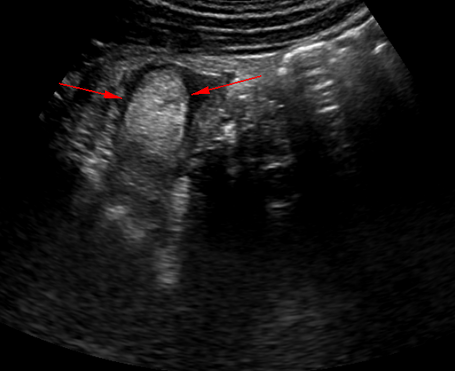

• 超音波検査

• CT検査